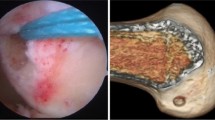

Second-look arthroscopic evaluation

Second-look arthroscopy was suggested at 2 years after surgery to compare the graft status and synovial coverage. The ACL graft evaluations were performed in accordance with the classification system described by Kondo and Yasuda [14], where the status was classified as A (intact), B (partial tear), or C (total tear) and the synovium coverage of the graft was graded as A (completely covered), B (partially covered), or C (barely covered).

Second-look arthroscopic evaluation

With respect to the graft status, in group 1, the ACL graft was graded as an A in 18 patients (94.7%) and a B in one patient (5.3%), while in group 2, it was graded as an A in 27 patients (87.1%) and a B in four patients (12.9%). The synovium coverage of group 1 was graded as an A in 17 patients (89.5%) and a B in two patients (10.5%) and in group 2, it was graded as an A in 24 patients (77.4%), a B in six patients (19.4%), and a C in one patient (3.2%). No significant differences between group 1 and 2 were found when evaluating the graft status or synovium coverage since some patients refused to receive second-look arthroscopy.